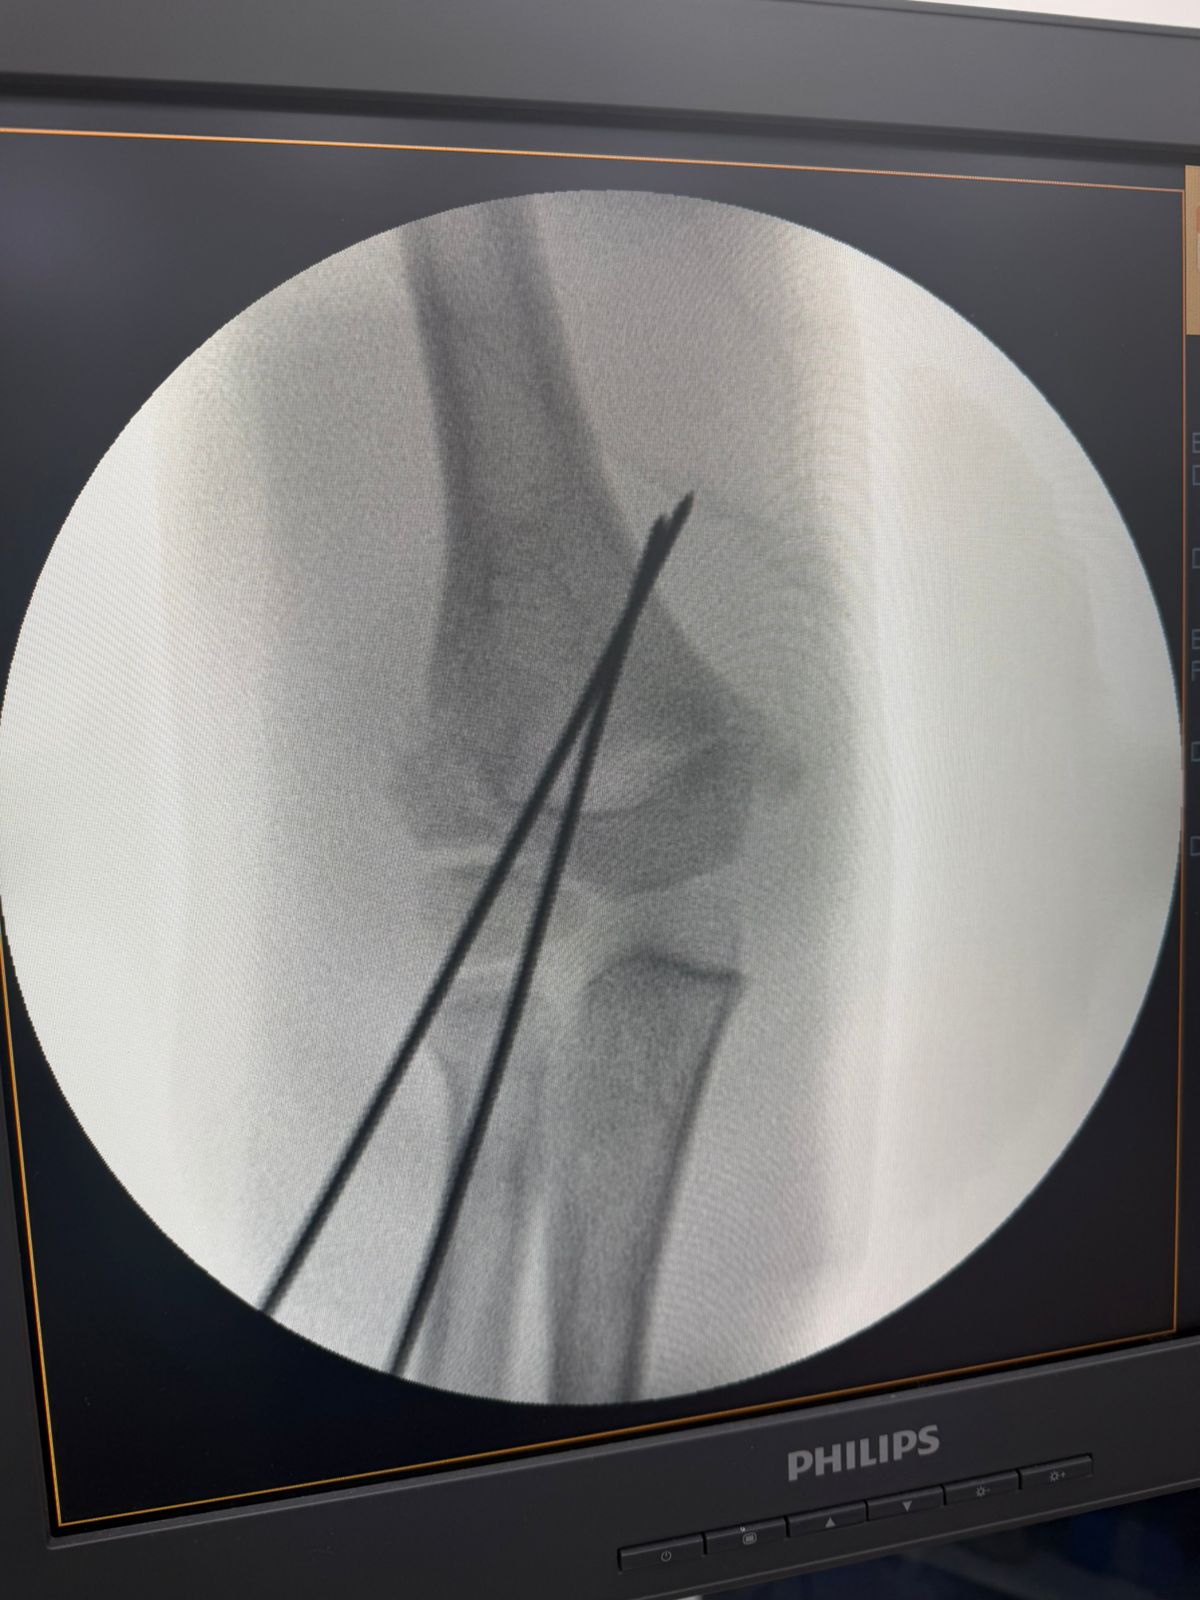

Essa transformação não está apenas nos números. Ela pode ser vista. As imagens que acompanham este texto mostram dois casos atendidos hoje no pronto socorro: crianças com fraturas no antebraço que foram avaliadas, diagnosticadas e operadas no próprio hospital, sem necessidade de transferência. Situações que exigem agilidade, equipe treinada e estrutura funcional.

Em outro episódio recente, uma criança em férias na cidade, com fratura grave de cotovelo, passou por todo o processo, do atendimento à alta hospitalar, em cerca de 10 horas, e já recuperada enviou um vídeo de agradecimento diretamente de Portugal, há dois dias.